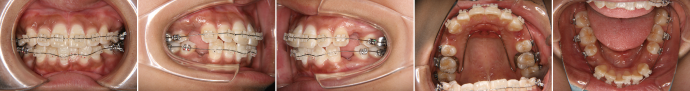

| 主訴 | 前歯が出ている |

| 年齢・性別 | 35歳 / 女性 |

| 治療方針 | 叢生も前歯の突出も大きいケース。小臼歯抜歯だけでは改善できないため、大臼歯の抜歯も行なった。 |

| 抜歯部位 | 上下顎左右小臼歯、左上第1大臼歯(計5本) |

| 使用装置 | マルチブラケット装置 |

| 治療期間 | 36か月 |

| リテーナー | 上顎インビジブル、フィックス、下顎インビジブル |

| 費用 | 885,000円(税別) |